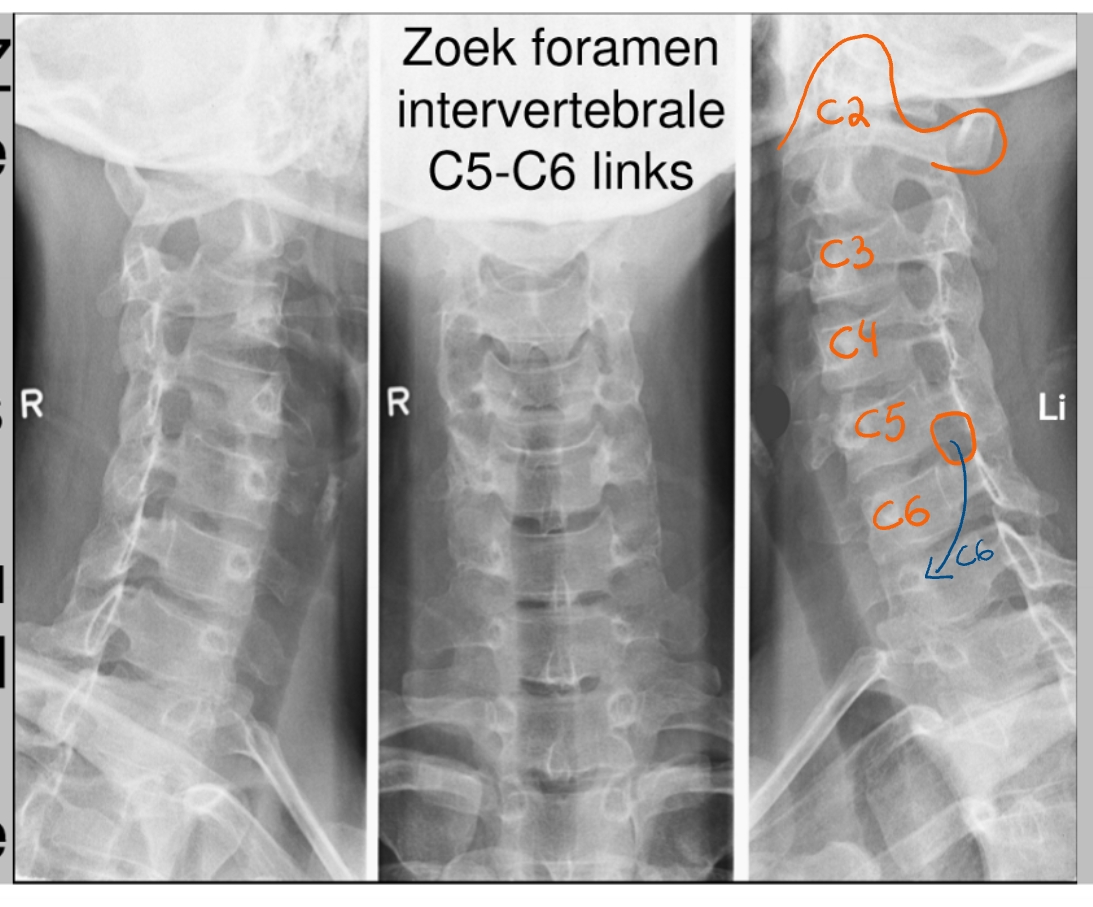

formamina intervertebrale

hier komen de spinale zenuwen uit

(linker beeld → linkerkaak)

schuine opname = oblique view

foramen intervertebrale C4-C5 (links)

daaruit komt spinale zenuw C5

processus uncinatus (linker)

pedikel (linker)